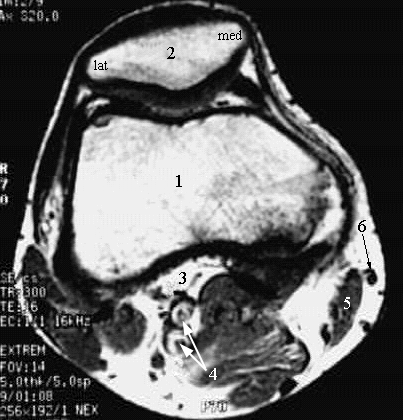

Lower Limbs: Knee Cross Zoom

1. Femur

2. Patella

3. Tendon of popliteus Muscle

4. Popliteal Vein and Artery

5. Sartorius Muscle

6. Great Saphenous Vein.